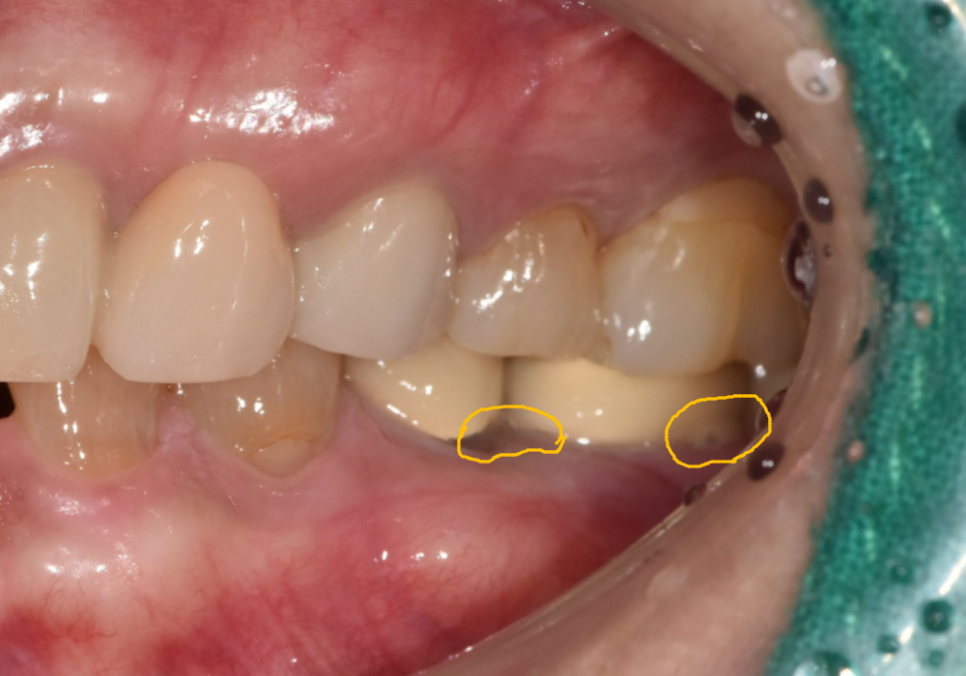

입안을 자세히 살펴보니,

보철물이 많이 닳아 낮아지면서

임플란트 나사 구멍이 드러나 있었고,

주변 잇몸은 붉게 부어올라

살짝만 건드려도 고름이 배어 나오는 상태였습니다.